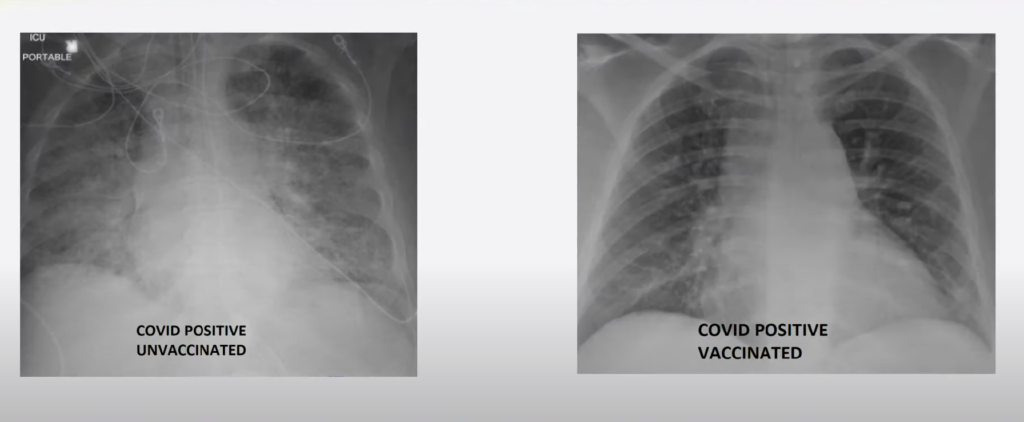

Ich slová potvrdzuje aj lekár Ghassan Kamel z St. Louis (Missouri), ktorý reportérke lokálnej televízie KSDK News ukázal röntgenové snímky pacientov s COVID-19. Kamel, ktorý je zároveň riaditeľom lekárskej JIS v nemocnici SSM Health, prostredníctvom snímkov znázornil, aký veľký rozdiel je medzi zaočkovanými a nezaočkovanými.

Pľúca plné baktérií a hlienov pri neočkovanom

V prípade neočkovaného pacienta bol röntgen pľúc výrazne biely, čo ukazuje poškodenie koronavírusom a znamená, že sa v pľúcach nachádzajú veci, ktoré tam nemajú čo robiť. Môže ísť o baktérie, hlieny alebo sekréty. „Pľúca by rozhodne prinajmenšom vyžadovali kyslík a v niektorých prípadoch by vyžadovali viac ako len kyslík,“ povedal doktor Kamel pre televíziu. „Môžu potrebovať ventilátor alebo intubáciu, mechanický ventilátor so sedatívami a zásadnú podporu života.“

Druhá snímka bola od pacienta, ktorý dostal prelomovú infekciu, ktorá podľa CDC tvorí len 1 % všetkých prípadov. Jeho snímka bola jasnejšia a obsahovala viac čiernej farby. Kamel vysvetlil, že pľúca sa na röntgene zobrazia čierne, keď sú naplnené vzduchom.

Zatiaľ čo neočkovaný jedinec mal prevažne biely röntgen, obraz očkovaného pacienta bol tmavší a na obrázku bolo viac čiernej. Pľúca zaočkovaného jedinca boli naplnené vzduchom, kým pľúca nezaočkovaného jedinca hlienmi prípadne baktériami.